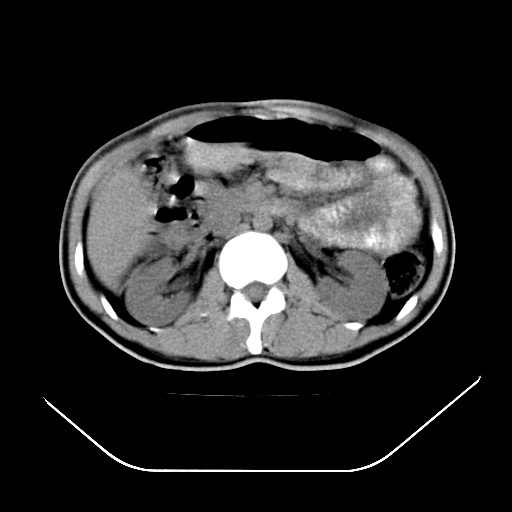

以下是引用深泽交通医院在2008-7-17 12:05:00的发言:[br]肝门淋巴结肿大;胆结石

以下是引用随光逐影在2008-7-17 17:52:00的发言:[br]1)胆囊结石。2)肝门及胰头区淋巴结肿大可能(原因不明);建议行进一步检查。

以下是引用卜一在2008-7-17 16:37:00的发言:[br]支持胆囊结石!!!至于胰头区病变——建议强化后再定论!